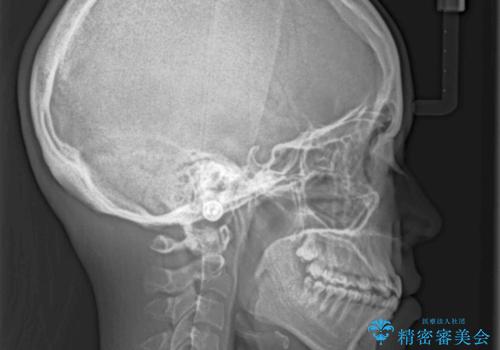

骨格的に下顎が前方位の受け口傾向であり、それが原因でクロスバイトとなっていました。

右奥の歯が180度回転していることで、噛む度にワイヤーに無理な力がかかったようで、頻繁にワイヤーが切れてしまいました。また、下顎を後方に移動させるためのアンカースクリューも脱離することが多く、治療期間が長くなってしまいました。